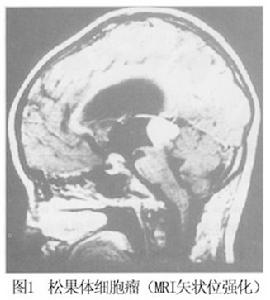

2.MRI 檢查 MRI 檢查腫瘤在T1 加權像呈等信號,也可呈低信號,而在T2加權像為高信號,矢狀位掃描有助於了解腫瘤的生長方向以及中腦受壓的程度,Gd-DTPA 增強對比亦為均一強化表現。